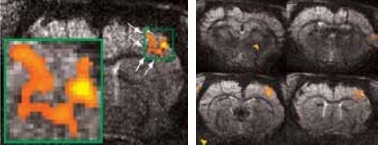

High resolution BOLD activation at 11.7 Tesla using the four-element array coil with a resolution of 75 x 75 x 1000 μm3 for detection of (left) sub-structures within S1, and activation within other regions along the neuronal pathway: S2 and thalamus

Figure 3. High resolution BOLD activation at 11.7 Tesla using the four-element array coil with a resolution of 75 x 75 x 1000 μm3 for detection of (left) sub-structures within S1, and activation within other regions along the neuronal pathway: S2 and thalamus. Image Credit: Bruker BioSpin Group

Matrices up to 256 x 256 were obtained with a four-element array coil, resulting in 75 x 75 x 1000 μm3 resolution. The activation becomes more resolved at this high resolution and allows the detection of sub-structures and shape in thalamus areas S1 and S2, as shown in Figure 3.